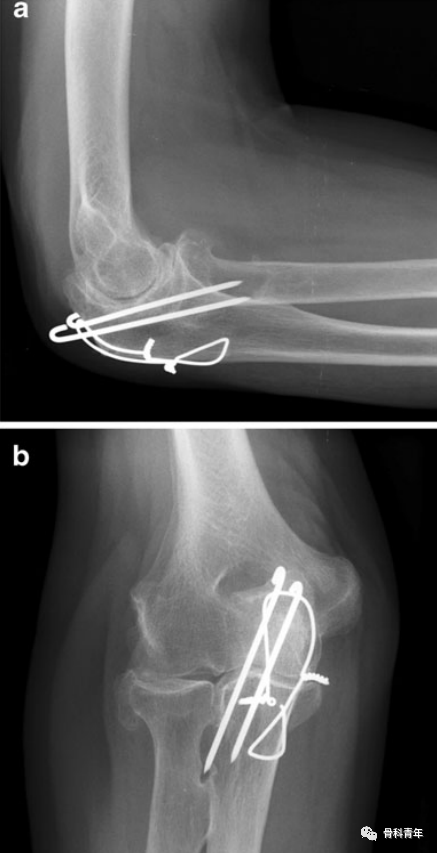

10项手术缺陷示意图。

1. 两枚克氏针不平行。平行克氏针可更好传导力量,避免力传导分散。两枚克氏针成角>5°被认为是不平行。2. 克氏针过长。尽管有学者认为克氏针穿出对侧皮质1cm范围内是可以接受的,但突出的克氏针可能导致神经血管损伤等严重并发症。因此认为克氏针穿出长度超过克氏针尖长度的2倍被认为是克氏针过长3. 克氏针向桡侧偏斜。克氏针在侧位上偏斜在前后位上可清晰辨认。4. 克氏针尾部固定不充分。克氏针尾部在剪断后因折弯180°,以适应尺骨鹰嘴顶部的形态,并有效避免软组织激惹。5. 髓内克氏针。在较早的研究中认为,克氏针置入髓内(非置入对侧皮质)也可取得较好的固定效果,但现普遍认为,克氏针穿入对侧皮质可提供更好的稳定性。6. 克氏针穿入关节。由于鹰嘴滑车呈弧形,克氏针从顶端置入过程中有可能中间部分置入关节内,如发现置入关节内,则应尽快调整或翻修,克氏针置入关节会影响关节活动,并引发创伤性关节炎。

不规范操作示例:病例1:该患者X线显示克氏针过长,远远超出对侧皮质;克氏针不平行,存在交叉;并利用了第三根克氏针。

病例2:该患者X线显示克氏针过长;单结固定;克氏针尾部折弯不够,未有效固定;克氏针穿入关节。

病例3:该患者X线显示克氏针向桡侧偏斜;克氏针过长。